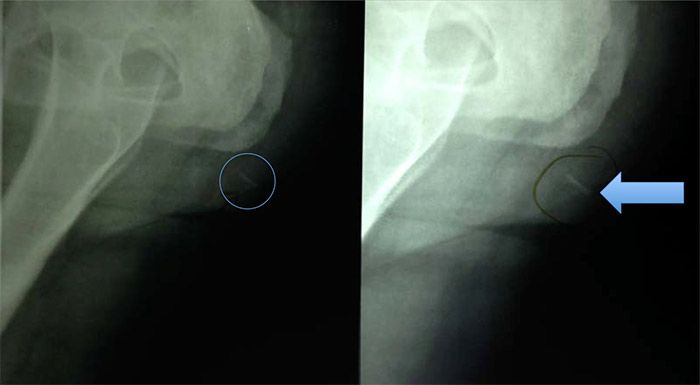

Broken Needle Radiography

On this picture, a needle 27g has been broken in 3 pieces during a gluteopexy by a physician.

The physician didn t take care about the hardness, unflexibility and curve of the needle.

Fortunately the 3 pieces have been eliminated by themselves without damaging the patient: No emergency surgery was needed, following the diagnosis of the radiologist.